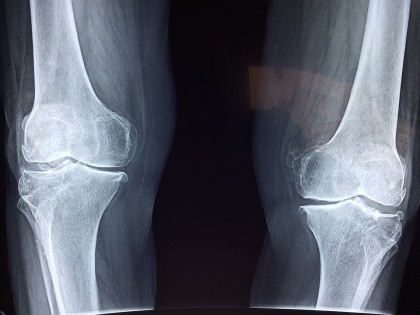

Studiul publicat în The Bone & Joint Journal s-a concentrat pe sistemul de clasificare CPAK (Coronal Plane Alignment of the Knee), care categorizează aliniamentele genunchiului bazându-se pe unghiul È™old-genunchi-gleznă È™i unghiul liniei articulare. Cercetătorii au analizat datele a 231 de pacienÈ›i care au suferit intervenÈ›ii de înlocuire a genunchiului între 2013 È™i 2019 din cauza osteoartritei.

Prin evaluări radiografice È™i chestionare postoperatorii privind simptomele, satisfacÈ›ia generală, nivelul de activitate È™i calitatea vieÈ›ii, s-a constatat că pacienÈ›ii la care alinierea genunchiului a fost modificată semnificativ în timpul intervenÈ›iei au avut rezultate pe termen lung mai puÈ›in favorabile. În special, cei la care unghiul liniei articulare a fost înclinat spre exteriorul genunchiului au raportat rezultate mai slabe.

Aceste descoperiri sugerează că reproducerea exactă a alinierii native a genunchiului în timpul intervenÈ›iei chirurgicale este esenÈ›ială pentru o recuperare optimă È™i o calitate îmbunătățită a vieÈ›ii postoperatorii. Studiul poate influenÈ›a practicile chirurgicale viitoare, promovând o abordare mai personalizată în planificarea È™i executarea artroplastiei totale de genunchi.